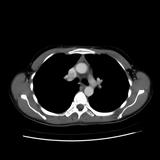

Case 8c Thymoma CT

Date: 03/27/2009

Views: 15480